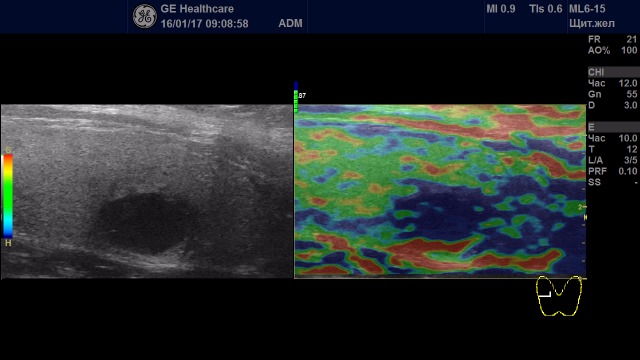

Образование с удовлетворительной эластичностью